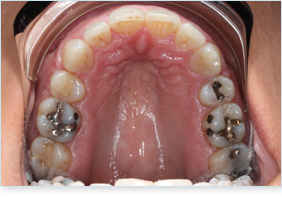

Clear Aligner

Benefits of Clear Aligners